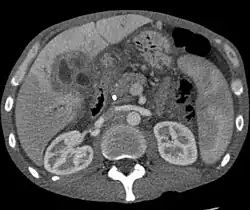

Abdominal imaging

Ultrasound of the liver and biliary tree is often used as the initial imaging modality in people with suspected obstructive jaundice.[50][51] Ultrasound can identify obstruction and ductal dilatation and, in some cases, may be sufficient to diagnose cholangiocarcinoma.[52] Computed tomography (CT) scanning may also play an important role in the diagnosis of cholangiocarcinoma.[53][54][55]